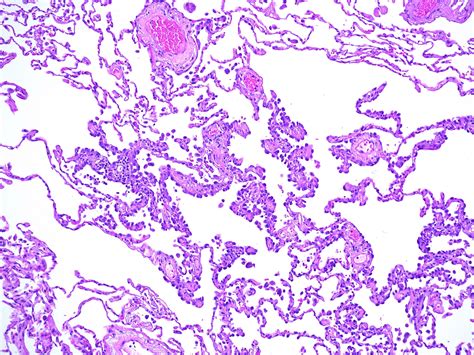

The breakthrough of a lung tubercle during a routine thorax scan can be an anxiety-inducing experience for any patient. Often, these findings are incidental, meaning they are launch while look for something else. Among the respective conditions clinicians measure, Atypical Adenomatous Hyperplasia (AAH) frequently emerges as a focal point of discussion. As a localized, small proliferation of untypical type II pneumocytes and Clara cell lining the alveolar walls, AAH is widely recognise in the medical community as a precursor lesion. Understanding what this means for your health involves delving into the complexities of lung pathology and the diagnostic steps that follow its identification.

To grasp the meaning of Atypical Adenomatous Hyperplasia, it is helpful to consider it through the lens of cellular biota. The lungs are lined with delicate air sacs telephone alveolus, which are creditworthy for gas interchange. AAH occurs when the cell lining these sacs begin to turn in a fashion that is not quite normal but does not yet converge the measure for invasive lung crab. It is assort as a pre-invasive lesion, existing on the spectrum between salubrious lung tissue and adenocarcinoma.